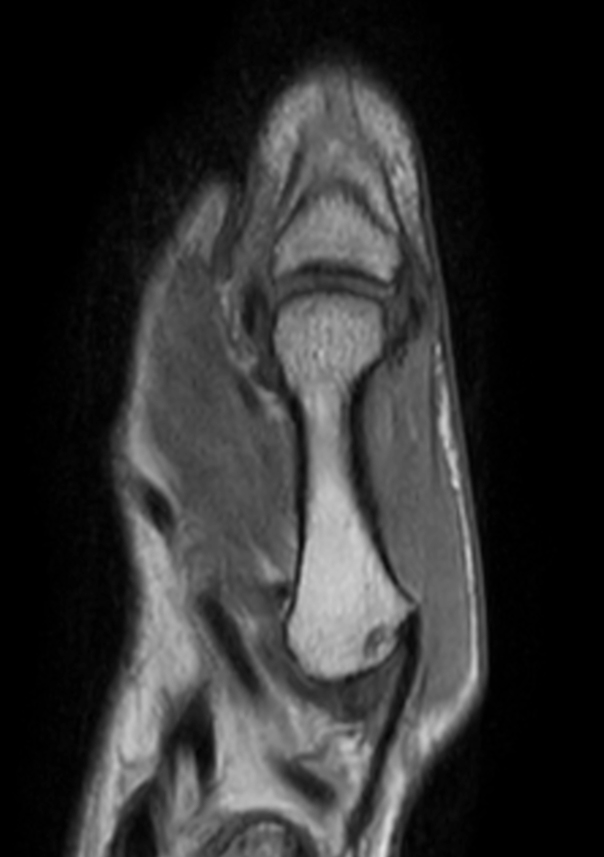

Patient with pathology on the thumb. ExamCard includes mDIXON XD TSE to achieve uniform, complete and consistent fat-free imaging. It simplifies the scan procedure by providing multiple image types in one single scan, including with/without fat suppression contrasts.

Coronal T1w TSE